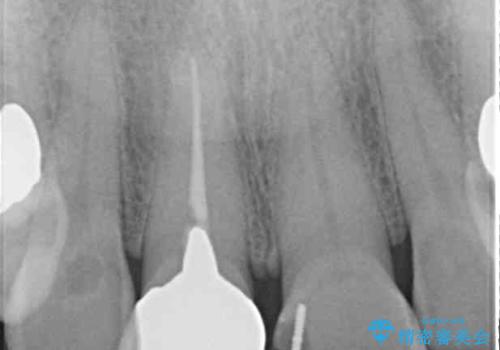

以前に前歯をぶつけた際、一方は神経を取り除いたためクラウンを装着し、もう一方は神経が残せたため一部修復をしていたとのことでした。

神経は残せていましたが、歯の色の変色が著しく、また広がった大きな形をしていたため、前歯2本をオールセラミッククラウンにて補綴することとしました。